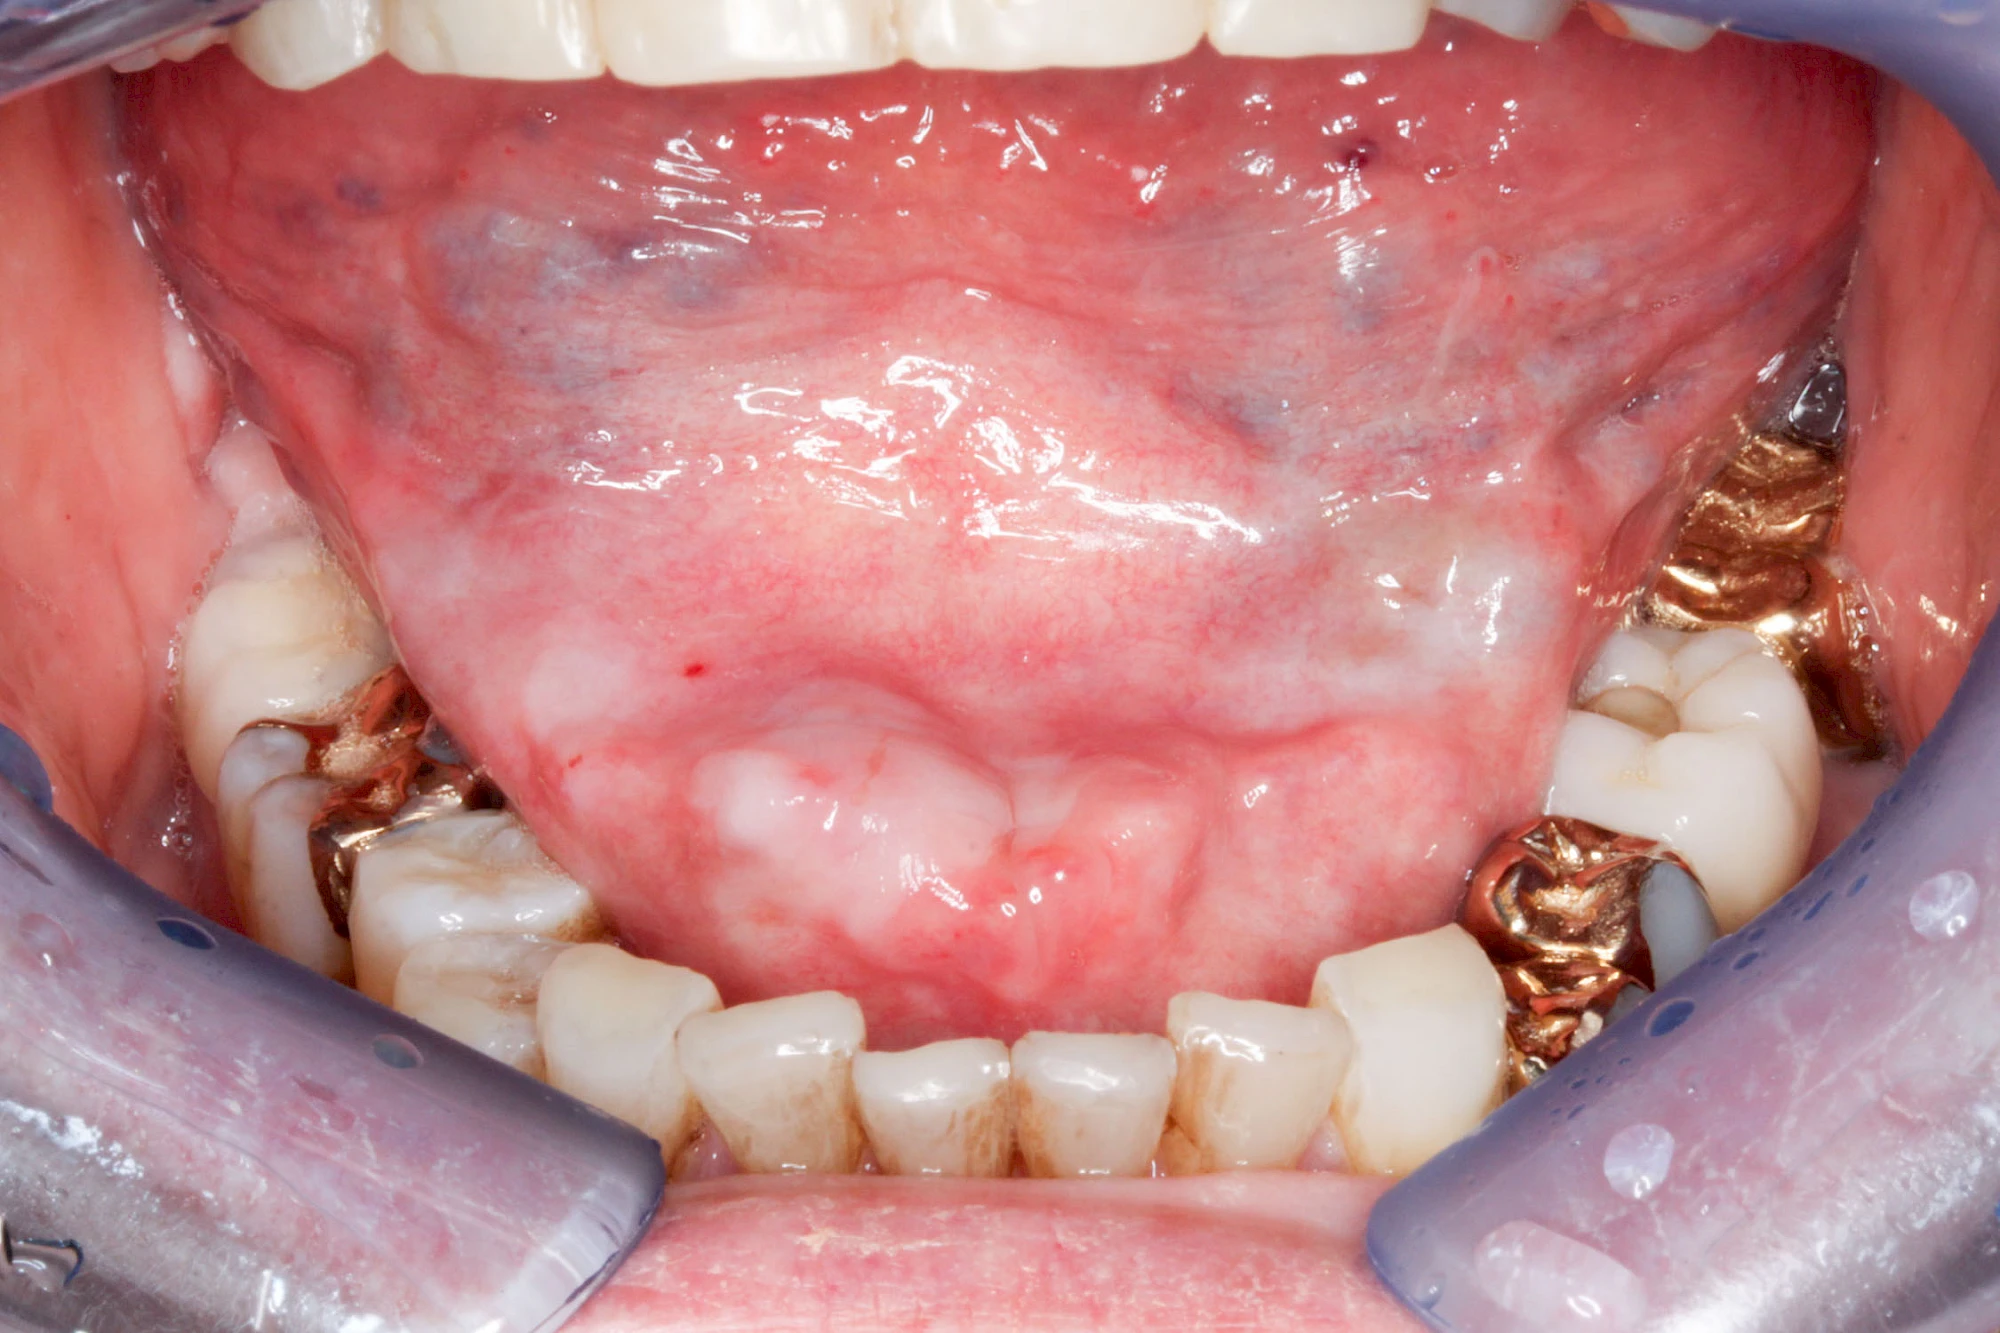

Besonderheiten: Wange & Mundboden

Milchiges bzw. gelbliches Sekret im Bereich der Speichelausführungsgänge entweder an den Wangeninnenseiten auf Höhe der ersten großen Backenzähne im Oberkiefer oder unter der Zunge können auf Entzündungen der großen Spreicheldrüsen hinweisen. Ebenso Schwellungen bzw. Auftreibungen, Rötungen oder spürbare Wärme einseitig unterhalb eines Ohrs und im Bereich des Kieferwinkels.

Einzündungen der kleinen Speicheldrüsen im Gaumen fallen dagegen durch kleine punktförmige Rötungen auf. Wenn ausreichende Flüssigkeitszufuhr und ggf. sanftes Massieren der Speicheldrüsen und der Ausführungsgänge (z. B. Parotitisprophylaxe) keine Verbesserung erzielen lassen oder wenn zusätzliche Symptome wie z. B. Fieber auftreten, sollte ein Arzt oder Zahnarzt hinzugezogen werden.